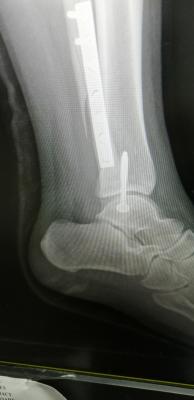

Mai scare me leg. My scan results are out. Ligament tendon all good. Just bone broken and one part dislocated. Broken part all screws. Dislocated, screwed back to strengthen.

just wait untill fractured heal...for time being slowly get range movement ankle and partially weight bearing if more than 6 week..and ostechondral injury cannot be seen in xray or ct scan..even sometimes mri also can be miss..u definitely have it as your medial malleolus fractured involving ankle joint which have cartilage over there..Mai scare me leg. My scan results are out. Ligament tendon all good. Just bone broken and one part dislocated. Broken part all screws. Dislocated, screwed back to strengthen.